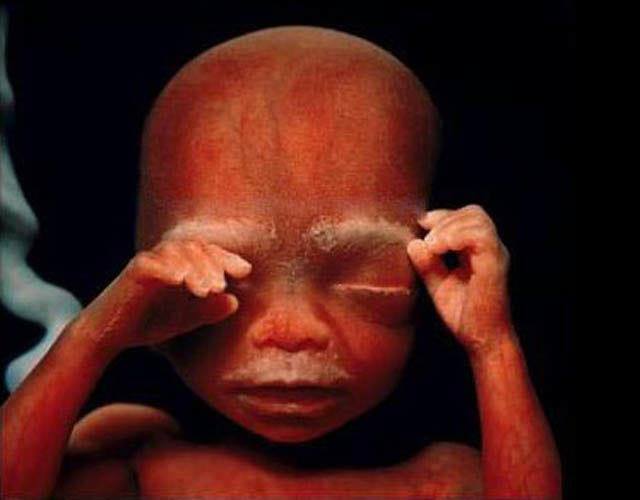

20.懷孕24週,雙手舉在臉前的小寶寶真的太萌了~

21.懷孕26週,寶寶再過不久以後,就要誕生在這個世界上了。